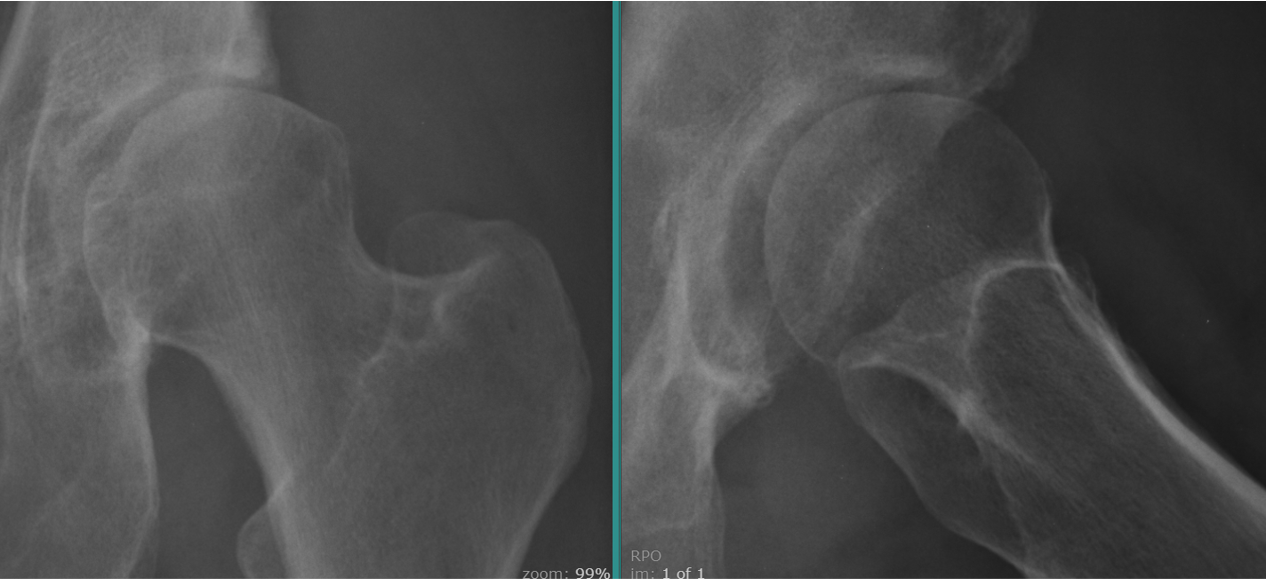

Imaging revealed a dysplastic hip with superior and anterior subluxation and joint space loss (figures 1a and 1b).